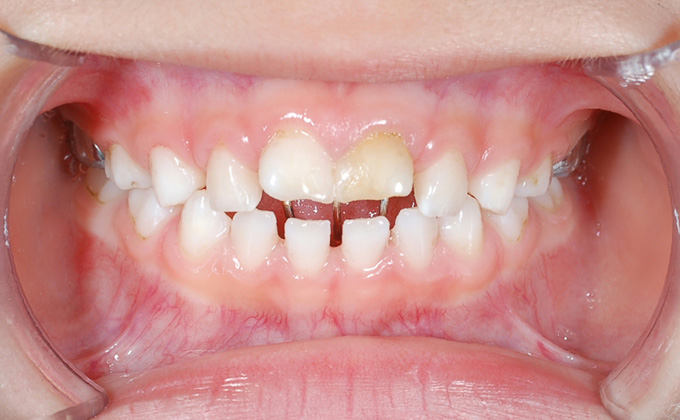

叢生(そうせい)

八重歯・乱ぐい歯など、歯が重なり合っている状態を言います。叢生の場合、歯ブラシが届かず汚れが残りやすくなります。

上顎前突(出っ歯)

上の歯が前に出ている状態を言います。歯が出ていると発音に影響が出ます。また折れたり唇を切ったりしやすく、見た目もあまりよくありません。